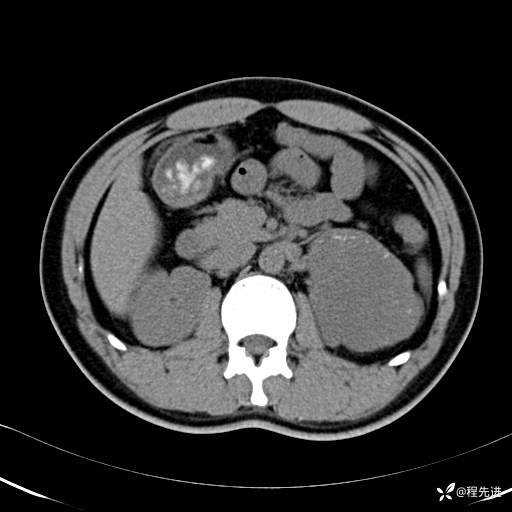

【腹盆】特别精彩病例|体检发现的左侧腹膜后占位期待您的精彩解读

患者年龄:25岁

简要病史:体检发现

CT平扫:(CT值:平扫,27HU,动脉期,27HU,门静脉期,31HU,平衡期,32HU)

平衡期: